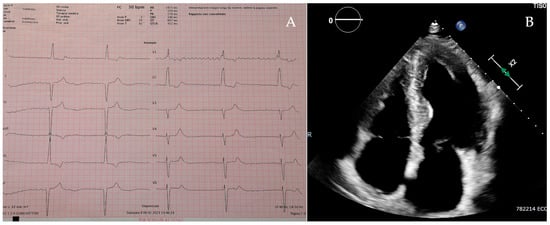

Patient 1 was a 70-year-old man admitted to the hospital with fatigue and shortness of breath. The 12-lead electrocardiogram showed a rhythm of atrial fibrillation complicated with a third-degree atrioventricular block and a ventricular rate of 30 beats per minute (Figure 2A), which required an urgent dual-chamber pacemaker implantation. The echocardiographic assessment revealed a severe LVH with a concentric pattern and an LVMWT of 20 mm at the level of the interventricular septum (Figure 2B), preserved left ventricular ejection fraction, severe left atrial enlargement, right ventricular hypertrophy and mildly reduced right ventricular function. The DBS showed a severe reduction in α-galactosidase A activity, and the gene sequencing identified a hemizygous pathogenic variant in the GLA gene: c.644A>G (p. Asn215Ser). CMR (performed with a 6 -week delay after pacemaker implantation) revealed decreased myocardial native T1 values and the presence of LGE in the infero-lateral wall with a subepicardial pattern. After the exclusion of extensive myocardial fibrosis [14], he started enzymatic replacement therapy (ERT).

Figure 2. Patient 1’s electrocardiogram (A) and apical 4-chamber view on the echocardiogram (B).